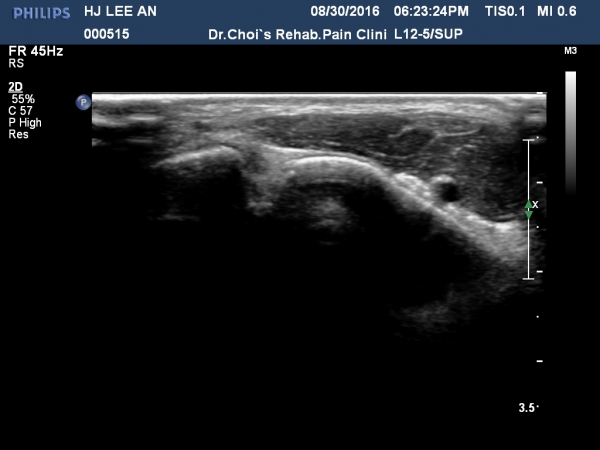

Àü°ÅºñÀδë Á¾´Ü¸é°Ë»ç¿¡¼­ ÀδëÀÇ Àú¿¡ÄÚ ºÎÁ¾ÀÌ °üÂûµÇ³ª °ß¿­°ñÀýÀº °üÂûµÇÁö ¾ÊÀ½(»çÁø 4, 5, 6, 7)

Àü°ÅºñÀδë ÃÊÀ½ÆÄÀ¯µµÇÏ ºÎÇϰ˻翡¼­ ÀδëÀÇ ºñ°ñºÎÂøºÎ¿¡¼­ Àδë¿Í ºÎÂøµÈ °ñÆíÀÇ ÀÌÅ»ÀÌ

°üÂûµÊ(÷ºÎµ¿¿µ»ó).